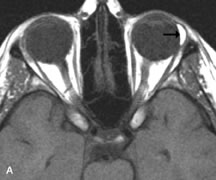

PATIENT PREPARATION Before MRI is performed, patients must be screened and prepared to avoid the potential hazards associated with the strong magnetic field. Patients who have ferrous aneurysm clips or cardiac pacemakers, who depend on life-support equipment, or who retain a possible metallic intraocular foreign body are not candidates for this imaging modality. MRI cannot be performed on obese patients who cannot fit into the bore of the magnet. Patients who are claustrophobic may not tolerate a prolonged period of study within the confines of the magnet, whereas others might do well if given a mild sedative. All worn metallic objects (e.g., necklaces, watches) should be taken off, credit cards set aside, and eye makeup removed before entering the room containing the magnet.5,20,34,35,36 NORMAL ORBITAL ANATOMY T1-weighted images provide the best anatomic details of the orbit because they display superior contrast resolution between normal structures (see Fig. 8). The vitreous has a long T1, resulting in an intermediate signal similar to brain, whereas the crystalline lens and sclera appear dark because of a longer T1 and short T2. The extraocular muscles, like all skeletal muscles, demonstrate a moderately long T1 and short T2 and highly contrast with the intense signal of the surrounding orbital fat (adipose tissue has an extremely short T1). The lacrimal glands appear as mottled areas of reduced intensity of the signal from the orbital fat in the lacrimal fossa. The optic nerves are seen with the same signal intensity as brain white matter and are hypointense relative to the orbital fat because their Tl is longer than the Tl of fat but shorter than the Tl of water. Cortical bone is not well delineated because it contains little free water, yielding minimal signal in MRI, and thus appears dark on all pulse sequences. This feature explains why MR images of the orbital apex and intracanalicular portion of the optic nerves are superior to comparable CT scans. Partial volume averaging of the bones in these regions obscures soft tissue details on CT images, whereas MRI reveals the signals only from the soft tissue structures with no cortical bone input. Bone marrow, on the other hand, is seen as a relatively intense signal because of its high fat content (see Fig. 8).37,38 T2-weighted pulse sequences are not ideal for imaging normal anatomy; however, they are particularly useful in revealing pathologic conditions (see Fig. 9). T2-weighted studies are most easily recognized by a bright vitreous signal. ORBITAL DISEASES Vascular Lesions Cavernous hemangiomas appear as well-circumscribed, smooth, usually intraconal masses that are isointense to muscle on T1-weighted images and hyperintense on T2-weighted images (Fig. 12). Patchy early enhancement is typically followed by diffuse, more homogeneous enhancement.39 The internal architecture of the mass, including septation and internal vasculature, may often be appreciated with high-quality orbital imaging.40 Lymphangiomas consist of ectatic vascular channels within a connective tissue stoma with varying degrees of lymphoid cellularity. On MRI, these tumors are typically poorly circumscribed, multicompartmental, and heterogeneous, often showing cystic dilations with fluid levels (Fig. 13). The signal characteristics within lymphangiomas vary considerably, reflecting cystic and solid components and the varying paramagnetic characteristics of blood at different stages of degradation.40–42 Acute hemorrhage appears hypointense on both T1- and T2-weighted formats. Methemoglobin present in subacute hemorrhage (3 to 14 days) leads to hyperintense signal on both T1- and T2-weighted images.41 A small percentage of lymphangiomas appear radiologically indistinct from orbital cavernous hemangiomas.43 Orbital varices are venous malformations that expand with increased systemic venous pressure, such as with Valsalva maneuvers. Because rapid acquisition of images during a Valsalva maneuver is important in imaging such a lesion, conventional or spiral CT is currently the modality of choice.44 MRI is an excellent modality for demonstrating enlargement of the cavernous sinus and dilation of the superior ophthalmic vein in patients with high-flow carotid-cavernous fistulas (Fig. 14).37MRA may be helpful in the evaluation of the venous outflow pattern. The rapidly flowing blood in these vascular structures carries the excited protons out of the section before they can be imaged, resulting in their dark appearance.5 In low-flow dural arteriovenous malformations, MRA may help define the arterial feeding vessels.45 Neural Lesions MRI is more effective than CT in delineating the intracranial optic nerves, chiasm, and optic tracts and, for this reason, is the preferred imaging modality in the evaluation of optic nerve disorders. The spatial relationships and image contrast of the orbital tissues with intraorbital optic nerve tumors is comparable between the two imaging modalities. The normal nerve is isointense to brain and appears enlarged and kinked owing to infiltration of an optic nerve glioma on T1-weighted images. Gliomas appear hyperintense on T2-weighted images and may be heterogeneous owing to cystic areas within the tumor. Contrast enhancement is variable.46 Intraorbital and intracranial optic nerve sheath meningiomas are usually isointense to cortical gray matter on Tl-weighted images and remain isointense on proton density studies (Fig. 15). Gd-DTPA is useful in delineating the intracranial extension of optic nerve meningiomas.7,47 The hyperostosis of bone and calcification associated with meningiomas are not demonstrated as well on MRI studies as on CT scans.20,37 Gd-DTPA–enhanced MRI also appears promising in the study of the permeability of the blood–brain barrier in selected optic neuropathies.22,48 MRI may reveal an enlarged optic nerve and some degree of contrast enhancement in cases of optic neuritis.49 Muscle Disorders Extraocular muscle enlargement in patients with thyroid-associated orbitopathy is demonstrated equally well with CT and MRI studies. However, the superior tissue contrast on MR images reveals better details of the relationships of the optic nerve to the thickened muscles at the orbital apex (Fig. 16).50 In addition, MRI may be able to differentiate between muscles that are enlarged as a result of edema and active inflammation and those enlarged because of fibrosis by their T2 relaxation times.21 Quantitative MRI was not found to be accurate in predicting the success of low-dose orbital irradiation.51 However, a muscular index relating the diameters of the rectus muscles to the bony orbital dimensions was useful in predicting optic nerve compression.52 MRI is also effective in imaging orbital tumors of mesenchymal origin, such as rhabdomyosarcoma, particularly in the assessment of extension into the anterior and middle cranial fossae (Fig. 17).37 The lack of any pathognomonic radiologic features necessitates rapid orbital biopsy when rhabdomyosarcoma is suspected. Osseous Lesions In general, CT is the imaging modality of choice when details of quantity and quality of bone are needed; however, abnormalities of bones can be detected indirectly by MRI. Cortical bone appears black (signal void) on MR images because of its low proton density and free-water content. The absence or discontinuity of the signal void of the orbital walls may represent bony destruction or fracture. Hyperostosis associated with prostate metastases or meningioma is visualized as areas of black smudging.50,53 Diseases in which the bone is replaced by pathologic tissues with a high free-water content, such as fibrous dysplasia, are well demonstrated on MRI. An intermediate signal intensity on T1-weighted images and hypointense signal on T2-weighted images is representative of fibrous dysplasia. Enhancement on post–Gd-DTPA MR scans is seen and is more evident in areas that are less mineralized.54 Cystic Lesions Dermoid cysts appear as rounded, well-defined lesions typically contiguous with an orbital bony suture. The high-intensity signal on T1-weighted images is attributed to the sebaceous-produced lipid contents (Fig. 18).31,50 Mucoceles may demonstrate a hypointense or hyperintense signal on MR images, depending on the concentration of proteinaceous or inflammatory fluid components. The integrity of the bony walls of the expanded sinus cavities cannot be assessed on MR as well as by CT.37,50,55,56 A high-signal intensity on Tl- and T2-weighted images is characteristic of orbital chronic hematic cysts because of the blood-breakdown products within the cysts.57 Trauma Although soft tissue relationships are usually better demonstrated on MRI, the evaluation of craniofacial bony trauma is preferable with CT. For example, prolapse of orbital fat through a fracture site and hemorrhage of adjacent tissues are demonstrated in an MR image, but the actual fractured bone is not imaged. Three-dimensional MRI of the orbit in subacute trauma has been described,58 although its precise role is not currently established. MRI has been suggested to be superior to CT in detecting intraorbital wooden foreign bodies.59,60 In a series of penetrating orbital injuries with organic foreign bodies, however, MRI was able to identify the foreign body in only four of seven cases.61 With an in vitro model for wood foreign body, McGuckin and colleagues concluded that CT was the imaging modality of choice.62 A careful history and, in selected cases, plain films to rule out a metallic foreign body are crucial before MRI is considered in patients with periocular trauma. MRI is particularly helpful in the detection and characterization of subperiosteal hematomas of the orbit (Fig. 19). They are most commonly seen in the subperiosteal space of the superior orbit as well-defined masses following a traumatic injury. The signal intensity varies depending on the acute, subacute, or chronic nature of the hematoma, based on the stage of blood degradation. Fresh hemorrhages are hypointense on T1-weighted images and hyperintense on T2 images. Hematomas that are 1 to 7 days old are hypointense on both T1- and T2-weighted images. T1-weighted images of hematomas more than a week old are hyperintense due to the oxidation of deoxyhemoglobin to methemoglobin, whereas the T2 images remain hypointense.63 Metastatic Tumors Breast carcinoma metastatic to the orbit has been demonstrated to be hypointense to the surrounding orbital fat on T1-weighted studies and hyperintense on T2-weighted images and has an affinity to the extraocular muscles (Fig. 20).50,64 The MRI characteristics of prostate carcinoma metastatic to the orbit have been described as involving the greater and lesser wing of the sphenoid, orbital roof, and optic canal. Diffuse bone hypertrophy with isointense or slightly hyperintense tissue on T1-weighted images represents the osteoblastic carcinomatous bone infiltration. Contrast enhancement is variable on T1-weighted and fat-suppressed images.65 Most other metastatic tumors also have a lower intensity signal on T1-weighted images and appear to displace or infiltrate normal orbital structures; however, their signal characteristics are variable on T2-weighted MR images.66 Many metastatic tumors demonstrate bright contrast enhancement with Gd-DTPA. Infectious Disorders MRI findings of preseptal and orbital cellulitis typically include increased signal intensities on T2-weighted images of the eyelids and orbital fat, respectively, due to the increased water content of the tissues. Since most cases of bacterial orbital cellulitis are associated with paranasal sinusitis, hyperintense signals of the affected sinuses may also be found on T2-weighted images as well as enhancement of polyps and granulation tissue on postgadolinium T1-weighted MR images. Subperiosteal abscess formation may occur due to contiguous spread of infection from the paranasal sinuses and appear on MRI as an area of intermediate signal on T1-weighted and proton-weighted MR images. The abscess may appear slightly hyperintense compared with muscle on T2-weighted scans with the necrotic contents having the greatest intensity.67 MRI and MRV are more sensitive than CT in revealing cavernous sinus thrombosis. Engorgement of the cavernous sinus, extraocular muscles, and ophthalmic veins is seen with hyperintensity of the thrombosed sinuses evident on all pulse sequences. The enlarged, thrombosed superior ophthalmic vein appears less hypointense than the normal contralateral ophthalmic vein, and hyperintensity within the lumen of the vessel may be seen on T1- and T2-weighted MR images.68 Inflammatory and Lymphoproliferative Lesions Inflammatory conditions of the orbit, both idiopathic (inflammatory pseudotumor) and those of known causes, have been found to be hypointense to fat and isointense to muscle on Tl-weighted studies and isointense or slightly hyperintense to fat on T2-weighted images (Fig. 21).50,64,69 The more fibrous or sclerosing varieties have less signal intensity on T2-weighted images. Marked enhancement is seen in pseudotumor infiltrates after gadolinium administration.70 The same signal characteristics are demonstrated in patients with Tolosa-Hunt syndrome, with mass lesions seen in the cavernous sinuses and orbital apices.71 Lymphomas have MRI characteristics similar to those of inflammatory lesions in that they are hypointense to fat and isointense to muscle on T1-weighted images (Fig. 22). They may appear hyperintense to fat on T2-weighted images, perhaps owing to less fibrosis than that seen in orbital inflammatory pseudotumor, although this is not a consistent finding.31,50,66 Lymphoid tumors typically enhance moderately after contrast injection. Unfortunately, studies have shown that tumor density and homogeneity are similar between inflammatory and malignant orbital infiltrates, and MRI cannot differentiate these lesions.72,73 Lacrimal Gland Tumors Lacrimal gland lesions present special problems in diagnosis and management. Pleomorphic adenoma (benign mixed tumor) should not be biopsied, but rather excised in toto. On the other hand, for lymphoma and inflammatory infiltrates, incisional biopsy is more appropriate than complete excision of the lacrimal gland. Thus, preoperative clinical and radiologic evaluation are especially crucial in planning appropriate surgical management. Pleomorphic adenomas demonstrate long T1 and T2 signal characteristics. They may show heterogeneity on T2-weighted images74 and moderate to marked enhancement with contrast.75 Signal characteristics of adenoid cystic carcinoma include hypointensity to fat on T1-weighted images, hyperintensity to fat with increased T2 weighting, and isointensity to fat on proton density-weighted studies (Fig. 23).31,75 Secondary bony alterations of the lacrimal fossa associated with lacrimal gland tumors, such as remodeling (benign mixed tumor) or destruction (adenoid cystic carcinoma), are seen indirectly on MR images; however, bone windows on CT scans provide better delineation of these changes. In contrast to the round or globular appearance of benign or malignant epithelial tumors of the lacrimal gland, lymphoproliferative tumors usually appear to be molding or draping onto the globe and the surrounding bony orbit. LACRIMAL DRAINAGE SYSTEM DISORDERS MRI with surface coils provides excellent spatial resolution and tissue-specific signal intensities of the lacrimal drainage system. These parameters have been found useful to more accurately demonstrate the extent of lesions in the lacrimal sac and differentiate long-standing mucoceles from solid tumors than CT.76 Physiologic studies in patients with tearing disorders now include MR dacryocystography, in which Gd-DTPA is either placed topically in the conjunctival fornix or injected by cannulation into the lacrimal sac. They provide a detailed morphologic and functional analysis of the lacrimal excretory system; however, they are no more sensitive than digital-subtraction dacryocystography or CT dacryocystography.77–79 INTRAOCULAR TUMORS On MRI, uveal melanomas have a typical appearance that helps to differentiate them from other primary and secondary intraocular tumors as well as choroidal detachments. Pigmented melanomas are hyperintense on Tl-weighted images, hypointense on T2-weighted studies, and hyperintense on proton density–weighted examinations (Fig. 24).30,31,50,80–82 These signal characteristics have been attributed to the paramagnetic properties of melanin because of stable free radicals that shorten the T1 and T2 relaxation times. Moderate enhancement is seen on postgadolinium T2-weighted images. Gadolinium-enhanced T1-weighted images are particularly sensitive in detecting choroidal melanomas.83 MRI may be less sensitive in detecting extrascleral extension of tumor than echography performed by an experienced ultrasonographer.84 Tumors metastatic to the choroid are hyperintense on T1- and T2-weighted images.24 The signal characteristics, however, may be similar to those seen with choroidal melanoma. Choroidal hemangiomas, on the other hand, have an intermediate signal on T1-weighted sequences and become hyperintense on T2-weighted images50 as well as proton density–weighted images.81 Retinoblastomas display moderate signal intensity on T1-weighted studies and a low signal on T2-weighted images.31,80,85 Calcification can be easily detected by CT and ocular ultrasonography but is not imaged by MRI.25,50 The presence of optic nerve involvement is best evaluated by MRI. ACQUIRED ANOPHTHALMIA When an eye is removed owing to tumor or trauma, an implant is typically placed in the intraconal space. MRI may be useful in defining the size, shape, and position of such orbital implants.86 Porous hydroxyapatite or polyethylene implants are preferred by many surgeons performing enucleation or evisceration. A porous implant offers the possibility of supporting a motility coupling peg to increase the movement of the overlying prosthesis. MRI with contrast is used by some surgeons to evaluate the degree of fibrovascular ingrowth in hydroxyapatite87 and porous polyethylene88 implants prior to motility peg placement. |